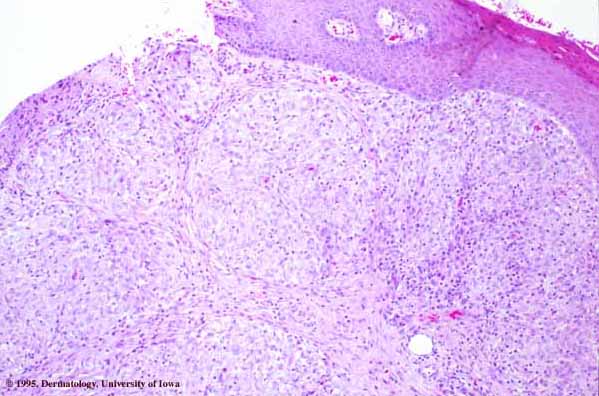

Tuberculoid leprosy, which may show granulomas in association with only a sparse lymphocytic infiltrate, can also be difficult to distinguish from sarcoidosis. Only 7% of cases of tuberculoid leprosy show acid-fast bacilli, and then only a few, so that they may easily be overlooked . The most likely place to find bacilli is within degenerated dermal nerves (the granulomas of tuberculoid leprosy form around dermal nerves that are undergoing necrosis). The granulomas of tuberculoid leprosy show small areas of central necrosis more often than those of sarcoidosis. In addition, the granulomas of tuberculoid leprosy, in contrast with those of sarcoidosis, follow nerves and therefore often appear elongated . Clinical correlation may be required to distinguish between these two diseases. For example, in the United States, leprosy virtually can be excluded if a patient has not been in an endemic area (either in a foreign country or where it is carried in armadillos domestically, e.g., Texas and Louisiana) or has not had prolonged close contact with another individual with the disease